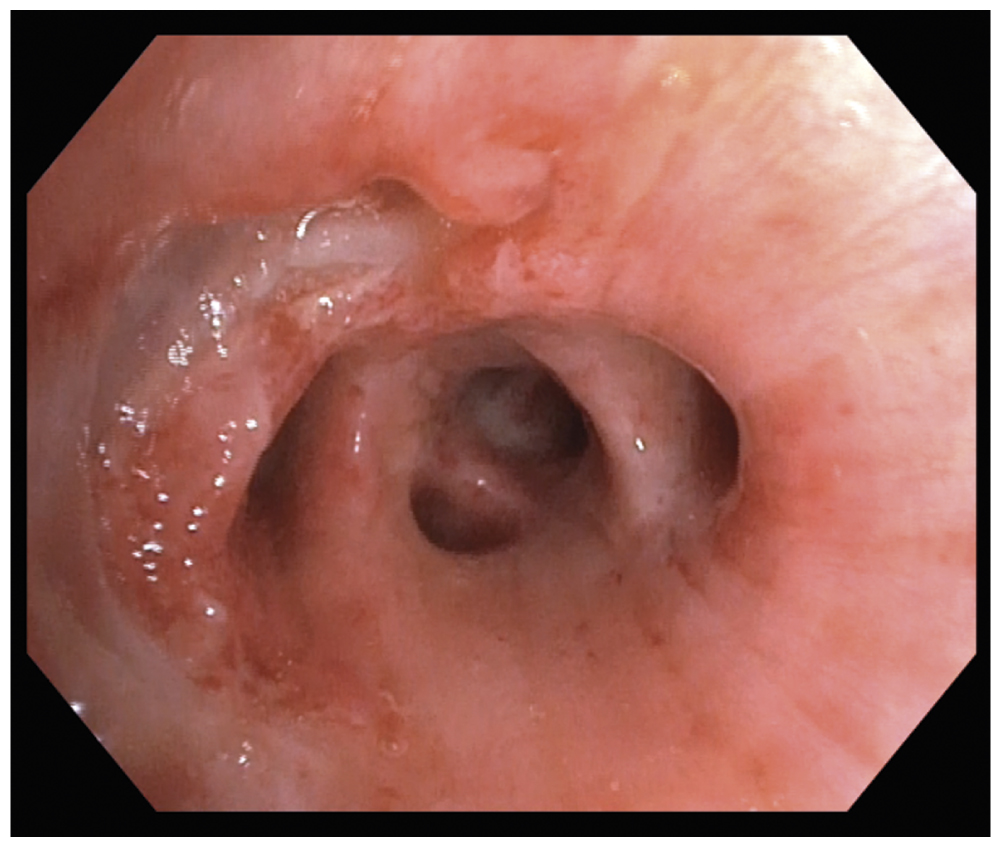

С использованием эндоскопических щипцов типа «аллигатор» выполнена бронхоблокация промежуточного бронха 3 блокаторами (полиуретановая медицинская губка) размером 8×10 мм (рис. 3).

Рис. 3. Эндоскопическая картина: окклюзия промежуточного бронха бронхоблокатором (стрелка — полиуретановая медицинская губка).

Fig. 3. Endoscopic picture: occlusion of the intermediate bronchus with a bronchoblocker (arrow — polyurethane medical sponge).

После окклюзии промежуточного бронха сброс воздуха по дренажам прекратился, верхняя доля правого лёгкого полностью расправилась, сохранялся ателектаз средней и нижней долей правого лёгкого, пневмоторакс купировался. Плевральный дренаж во 2 межреберье был удалён. В послеоперационном периоде отмечен регресс дыхательной недостаточности: pCO2 55 мм рт. ст., pO2 90–92 мм рт. ст., сатурация 99–100%. По данным СКТ на 6 сут после выполнения ЛТБС в просвете промежуточного бронха справа определялось инородное тело (блокаторы), полностью перекрывающее просвет бронха. Средняя и нижняя доли резко уменьшены в объёме, бронхиальное дерево и паренхима их полностью безвоздушны, пневмомедиастинум и воздушная эмфизема мягких тканей регрессировали (рис. 4).